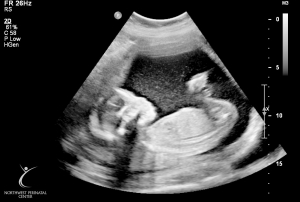

Last Ultrasound